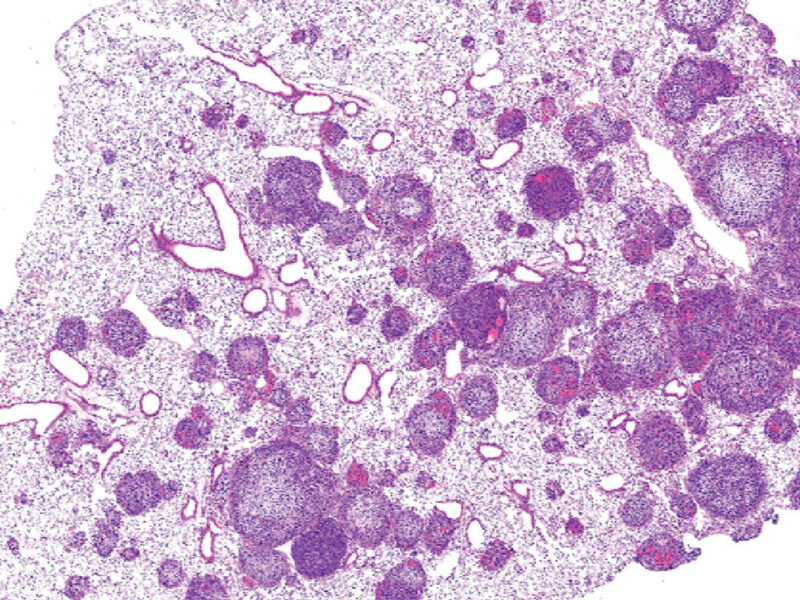

MDM2 is overexpressed in many types of cancer, such as osteosarcoma, and these cancers would benefit from persistent alternative splicing of MDM2 to downregulate MDM2 expression, reactivate p53, and sensitize these tumors to current therapies.